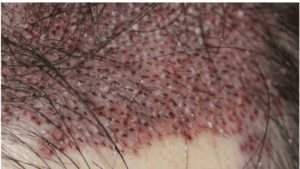

連日、2000Gを超える手術が続きました。移植の株数が多くなればなるほど、手術の難易度が増し、我々医師だけでなく、移植看護師の経験や実力がものを言います。 さて、本日はその大事な移植看護師の実力や質について、たくさんの看 […]

植毛手術において、FUE法(follicular unit excision)(後頭部や側頭部などの採取部から1つずつ特殊な器具を用いて毛包単位で採取していく方法)でもクリニックにより方法や工程が全く異なります。 施術工 […]